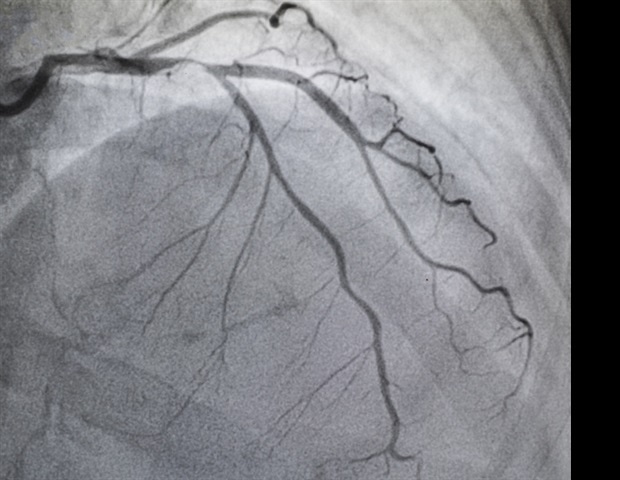

Η στένωση αορτής συμβαίνει όταν το ασβέστιο συσσωρεύεται σταδιακά, περιορίζοντας τη ροή του αίματος. Αποτελεί μία από τις πιο συχνές και σοβαρές παθήσεις των βαλβίδων, επηρεάζοντας πάνω από 2,5 εκατομμύρια Αμερικανούς άνω των 75 ετών. Συμπτώματα όπως η δύσπνοια, η δυσκολία βαδίσματος και η κόπωση συχνά συγχέονται με φυσιολογικές εκδηλώσεις της γήρανσης, προκαλώντας έτσι υποδιάγνωση και υποθεραπεία. Η συνήθης θεραπεία για την AS είναι η AVR, η οποία πραγματοποιείται είτε μέσω λιγότερο επεμβατικών διαδικασιών με καθετήρα (TAVR) είτε μέσω ανοικτής καρδιάς (SAVR). Ωστόσο, μόλις το 50% των ασθενών με σοβαρή συμπτωματική AS υποβάλλονται σε AVR, αφήνοντας πολλούς ηλικιωμένους ασθενείς με αυξημένο κίνδυνο καρδιακής ανεπάρκειας και θανάτου.